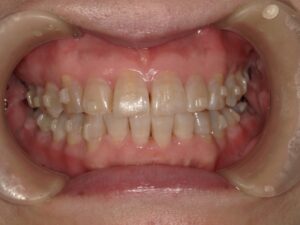

歯冠長延長術

歯ぐきを切除すると共に歯を支える歯槽骨を削って、歯茎を大きく下げるイメージです。歯を長く見せる術式になります。歯肉と骨の両方を削合するので、効果を得やすいですが比較的大きな侵襲がかかります。歯が長く、歯を支える骨が十分にある歯が適応です。ただし今まで口腔内に出ていなかった歯根が口腔内に露出することになるので、知覚過敏のリスクがあります。歯そのものの長さが短いと、歯を支える骨が少なくなり歯が揺れてしまうので、適応症ではありません。

歯肉整形

歯冠長延長術とは少し違い、メスで余分な歯ぐきだけを切除し、歯を長く見せます。ですから比較的低侵襲で行えます。歯を支える骨に問題なく、歯肉だけが多い場合が適応です。こちらも、今まで口腔内に出ていなかった歯根が露出するので知覚過敏のリスクがありますが、歯冠長延長術よりも低リスクです。切除量はさほど大きくできないので、効果は限定的です。